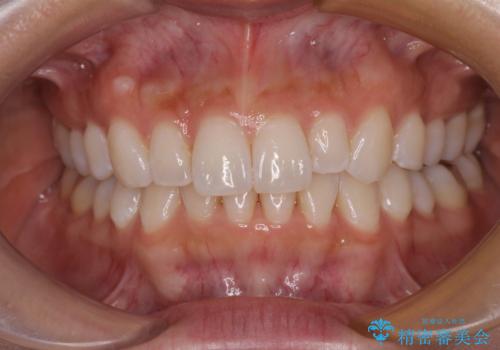

【モニター】前歯のデコボコと小さい前歯 インビザライン矯正とオールセラミッククラウン補綴治療

- 前歯の歯並びと生えてきたときから小さい前歯を気にして来院された患者様です。

上下前歯の歯列不正はインビザラインにより整え、その後に、矮小歯の前歯をオーダーメイドタイプのオールセラミッククラウンにて補綴治療することとしました。

セラミッククラウンにて大きさを変更することを前提に矯正治療を開始したため、大変満足のいく仕上がりとなりました。